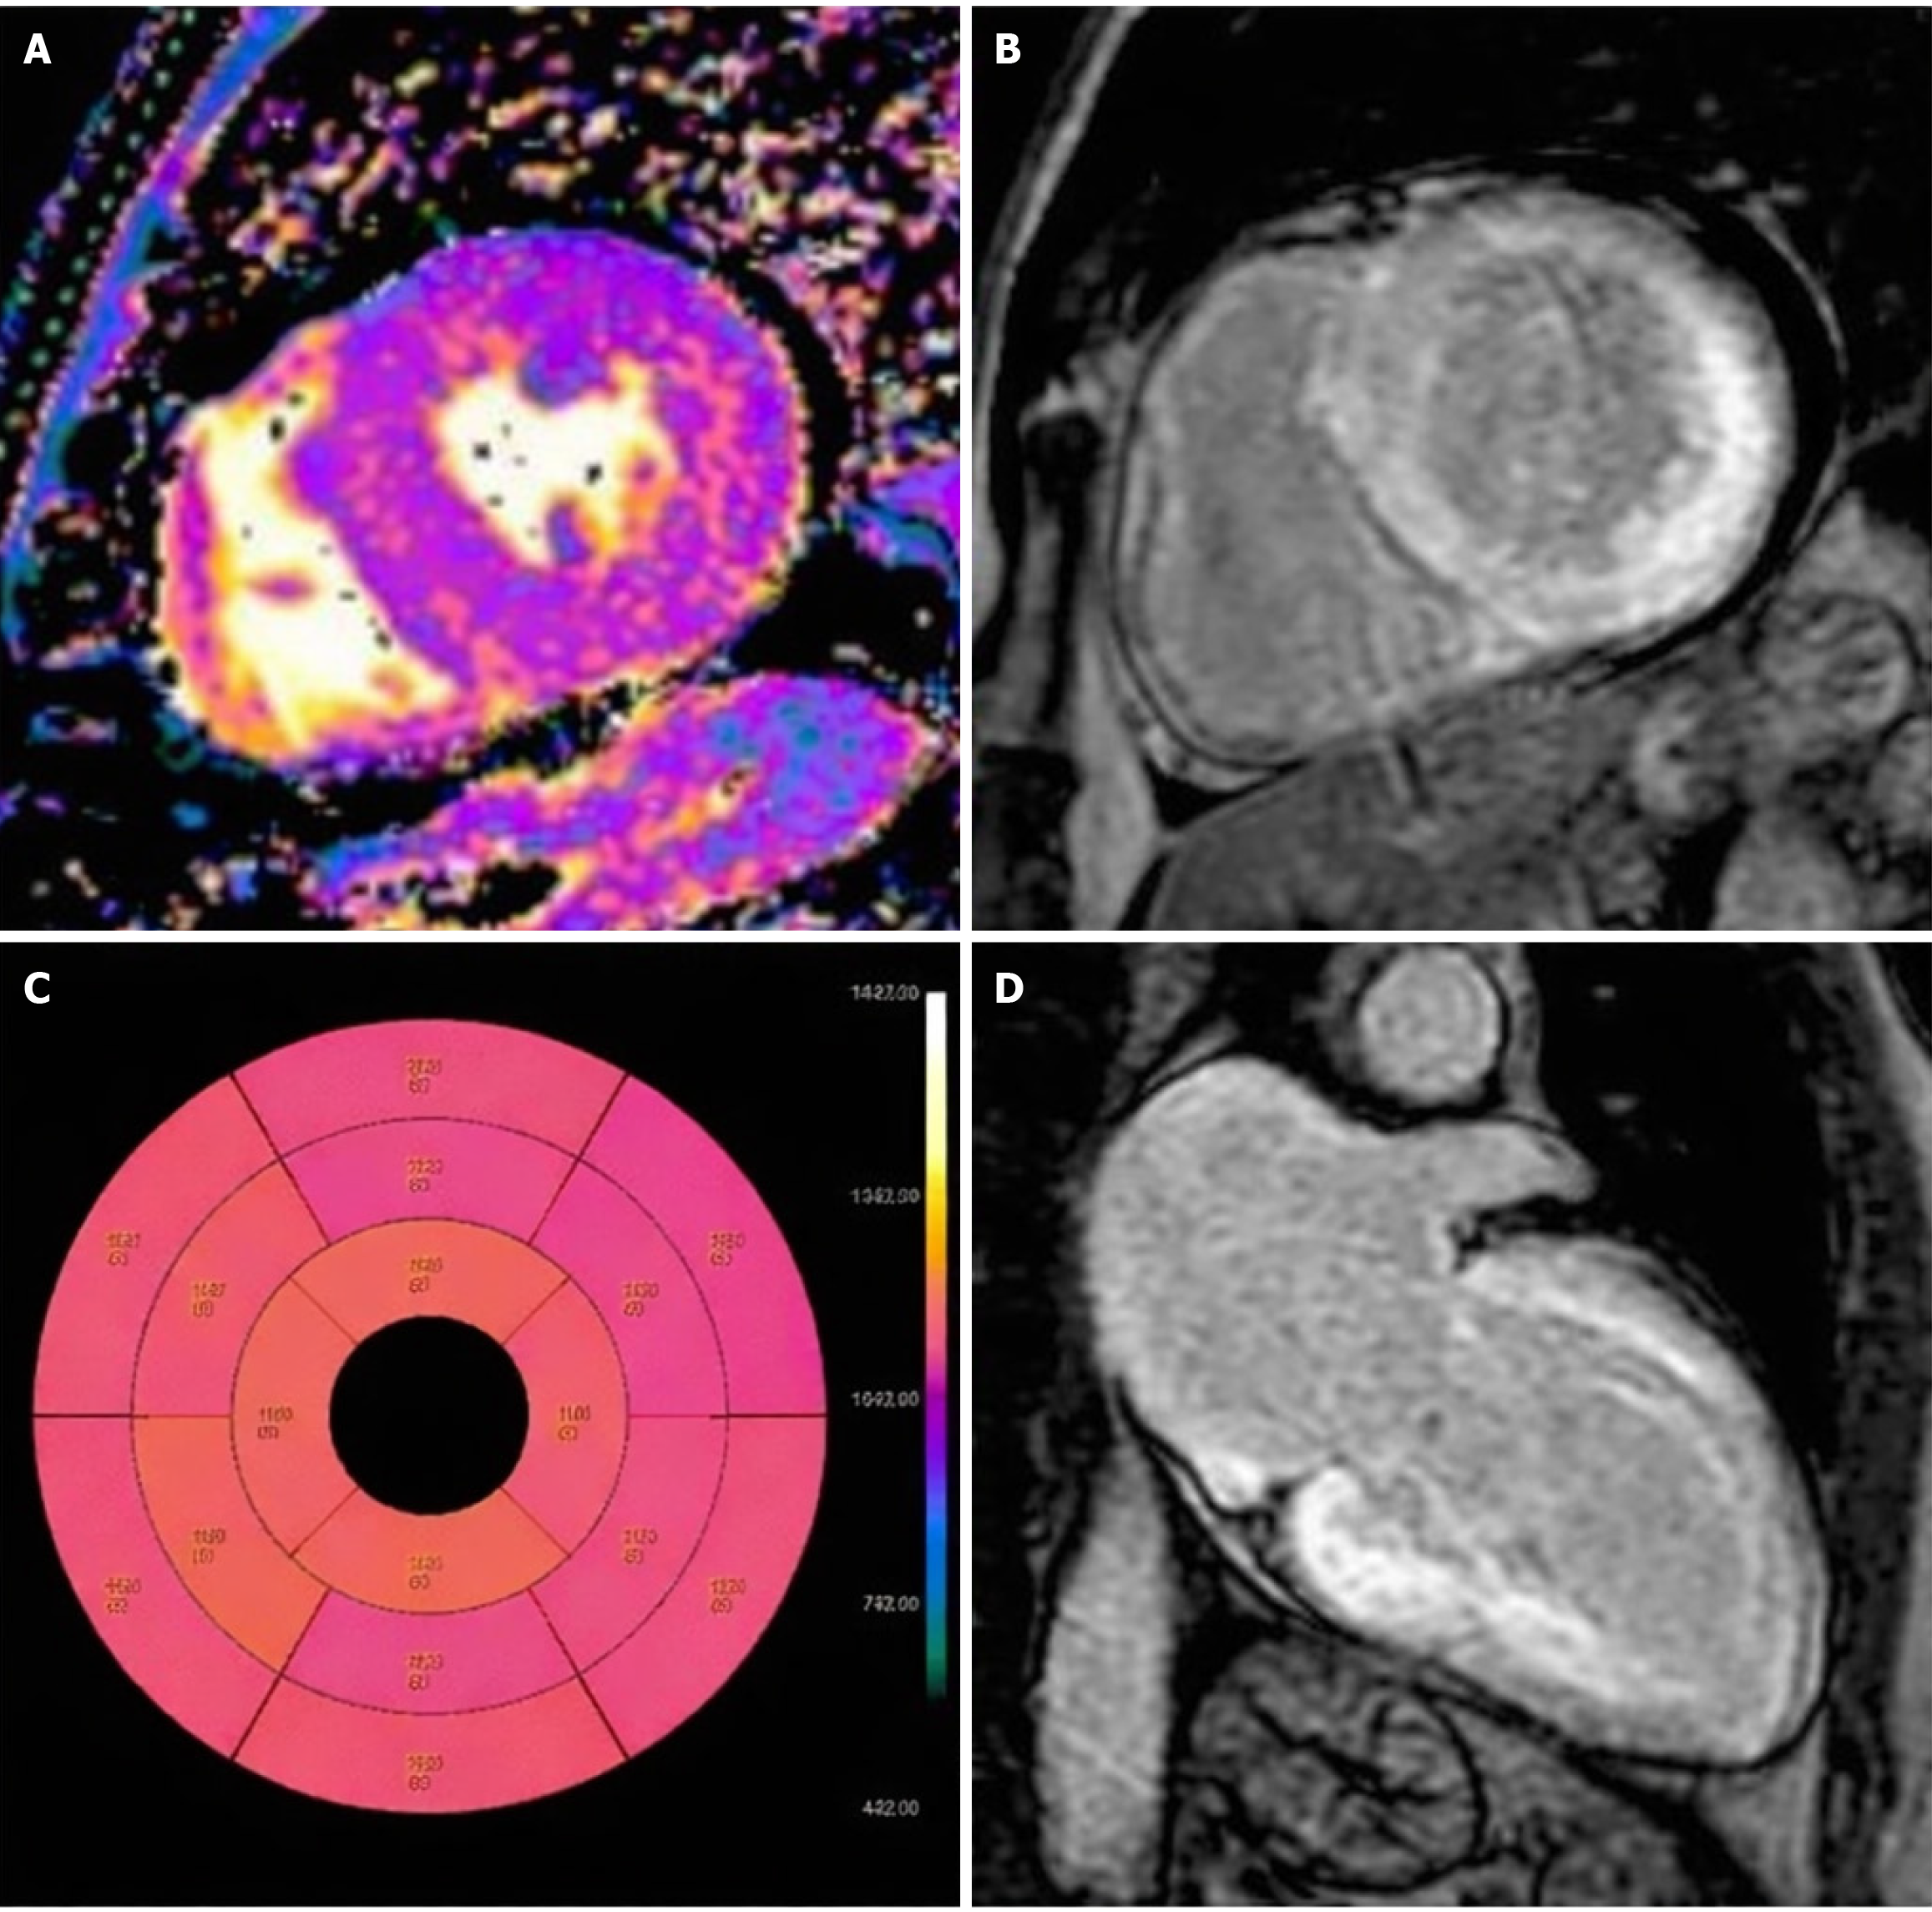

Figure 2 Patient diagnosed with endomyocardial biopsy.

A: T1 native mapping demonstrates abnormally high values in all entire left ventricle (LV) walls in cardiac amyloidosis; B: Diffuse transmural LV and subendocardial right ventricle (RV) late gadolinium enhancement (LGE) in two-chamber short; C: Bulls-eye map of T1 native; D: Diffuse transmural LV and subendocardial RV LGE in long axes[26]. Citation: Maggialetti N, Torrente A, Lorusso G, Villanova I, Ficco M, Gravina M, Ferrari C, Giordano L, Granata V, Rubini D, Lucarelli NM, Stabile Ianora AA, Scardapane A. Role of Cardiovascular Magnetic Resonance in Cardiac Amyloidosis: A Narrative Review. J Pers Med 2024; 14: 407. Copyright© The Authors 2024. Published by MDPI. The article is open access (Supplementary material).